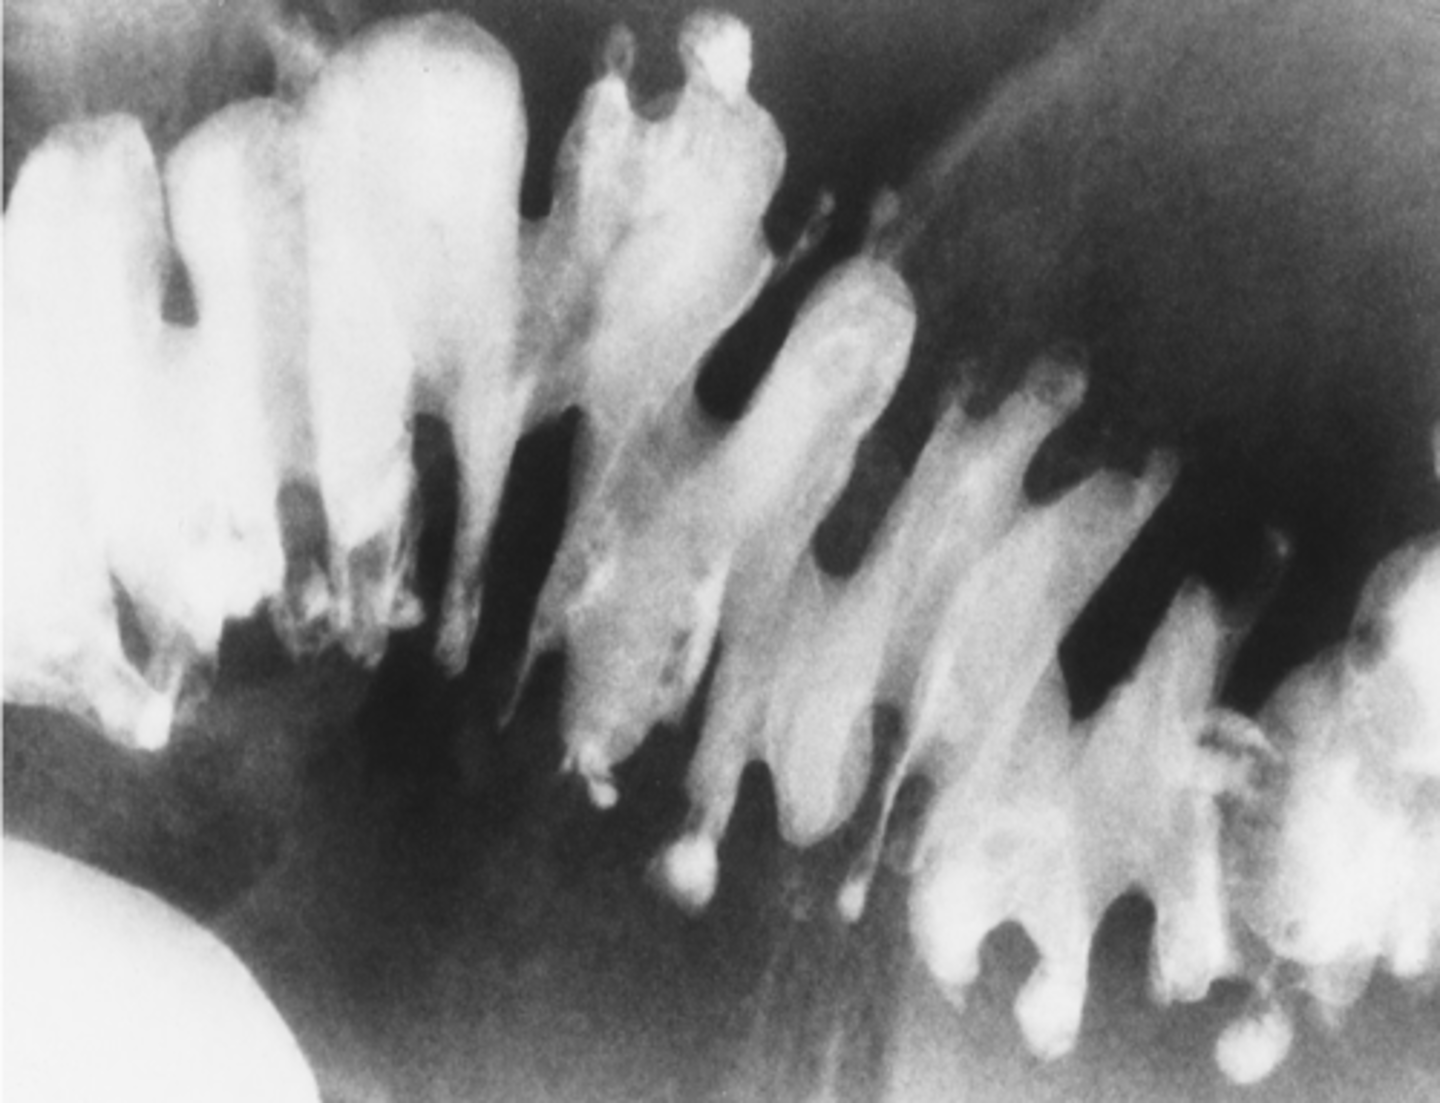

Crohn's disease

- skip lesions, discontinuous

- affected area: small bowel & duodenum

- string sign: tubular narrowing